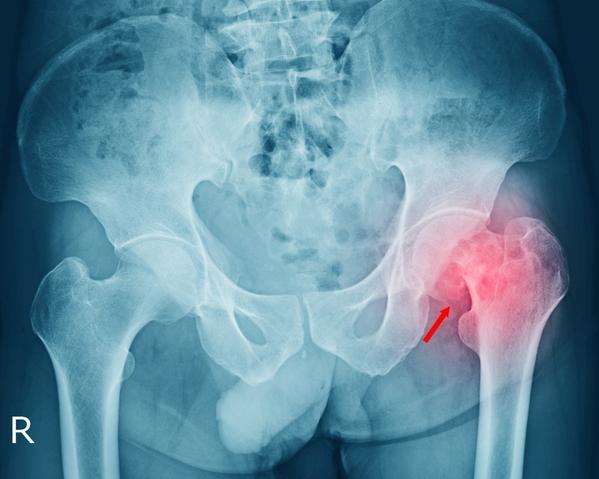

Chondrosarcoma Surgery in Mumbai – Restoring Bone Health with Precision

Chondrosarcoma Surgery in Mumbai – Restoring Strength Through Specialized Care

Chondrosarcoma Treatment in Mumbai – Expert Care for Complex Cartilage Cancer